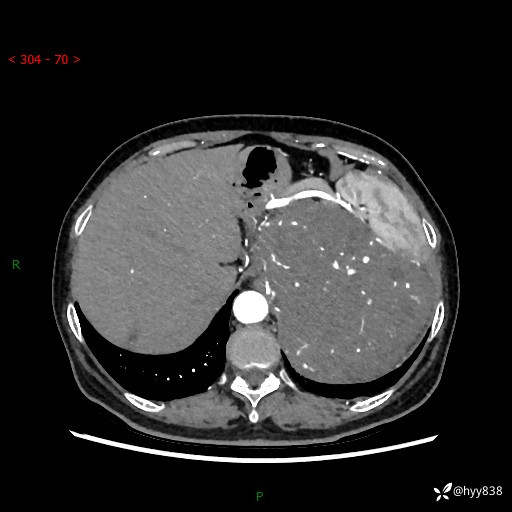

据说只有腹膜后,才能见到如此巨大的肿块---(有结果)

主诉:发现腹膜后占位1周

简要病史:患者1周前因头晕在当地第二人民医院检查发现左侧腹膜后区巨大富血供占位性病变,患者自诉腹部稍硬,无其他不适,无血尿,无腰痛等不适,患者为求进一步治疗来我院,门诊以“腹膜后占位性病变”收入我科。 起病以来,患者精神、饮食、睡眠可,大便正常,小便如上述,体力体重无明显改变。

临床诊断:腹膜后占位

腹部CT增强(动脉期+静脉期 ) ---平扫外院